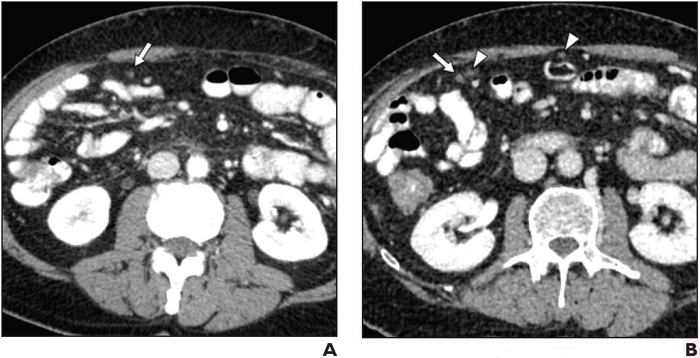

Positive oral CT contrast improves detection of malignant deposits in intraabdominal nonsolid organs

Leesburg, VA, March 16, 2022 According to ARRS’ American Journal of Roentgenology ( AJR ) , the selection of oral contrast agent and optimization of bowel preparation for oncologic CT could help avoid potentially severe clinical consequences of missed malignant deposits.

“CT has suboptimal NPV for malignant deposits in intraabdominal nonsolid organs,” wrote corresponding author Benjamin M. Yeh of the University of California, San Francisco. “Compared to neutral material, positive oral contrast material improves detection, particularly with adequate bowel filling.”

Yeh and team’s retrospective study included 265 patients (133 men, 132 women; median age, 61 years) who underwent an abdominopelvic CT examination where the report did not suggest presence of malignant deposits and subsequent CT examination within 6 months where the report indicated at least one unequivocal malignant deposit. Examinations used positive (iohexol; n=100) or neutral (water; n=165) oral agents. While reviewing images to assess visibility of deposits, a board-certified abdominal radiologist also assessed adequacy of bowel filling with oral contrast material.

NPV of CT for detection of malignant deposits in intraabdominal nonsolid organs was 65.8% for examinations using positive oral contrast material with adequate bowel filling, 45.2% for positive oral contrast material with inadequate bowel filling (p=.07), and 35.2% for neutral oral contrast material regardless of adequacy of bowel filling (p=.002).